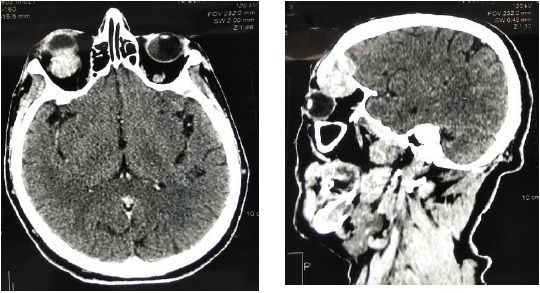

Мягкотканые образования в костях и мягких тканях выявлялись по данным компьютерной томографии (КТ) и магнитно-резонансной томографии (МРТ) (рис. 1–3). Эти инструментальные методы обследования позволили подтвердить наличие плазмоцитомы у данной категории больных (в костях грудной клетки, в позвоночнике, в глазнице).

Рис. 3. Мягкотканое образование в орбите глаза слева при компьютерной томографии